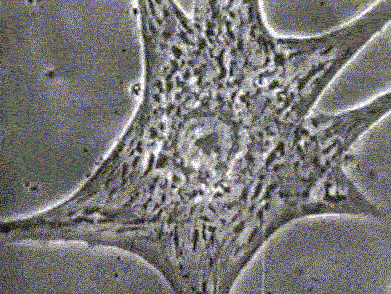

6乳腺癌细胞